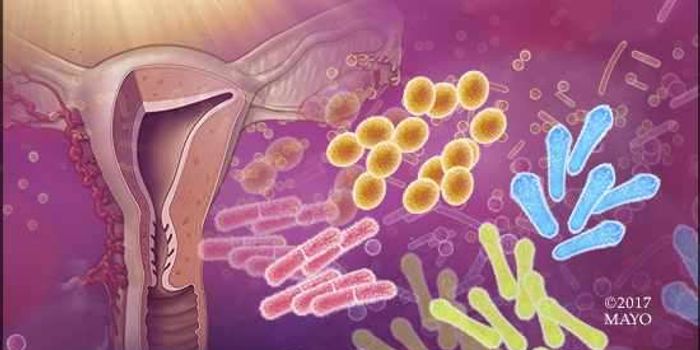

OCT 13, 2022CancerThe cancer microbiome, the collection of microorganisms, including bacteria, viruses, and fungi, that live in or around ...

JUN 07, 2016MicrobiologyThere’s no such thing as sterile. That’s my opinion, at least. Researchers from the University of North Caro ...